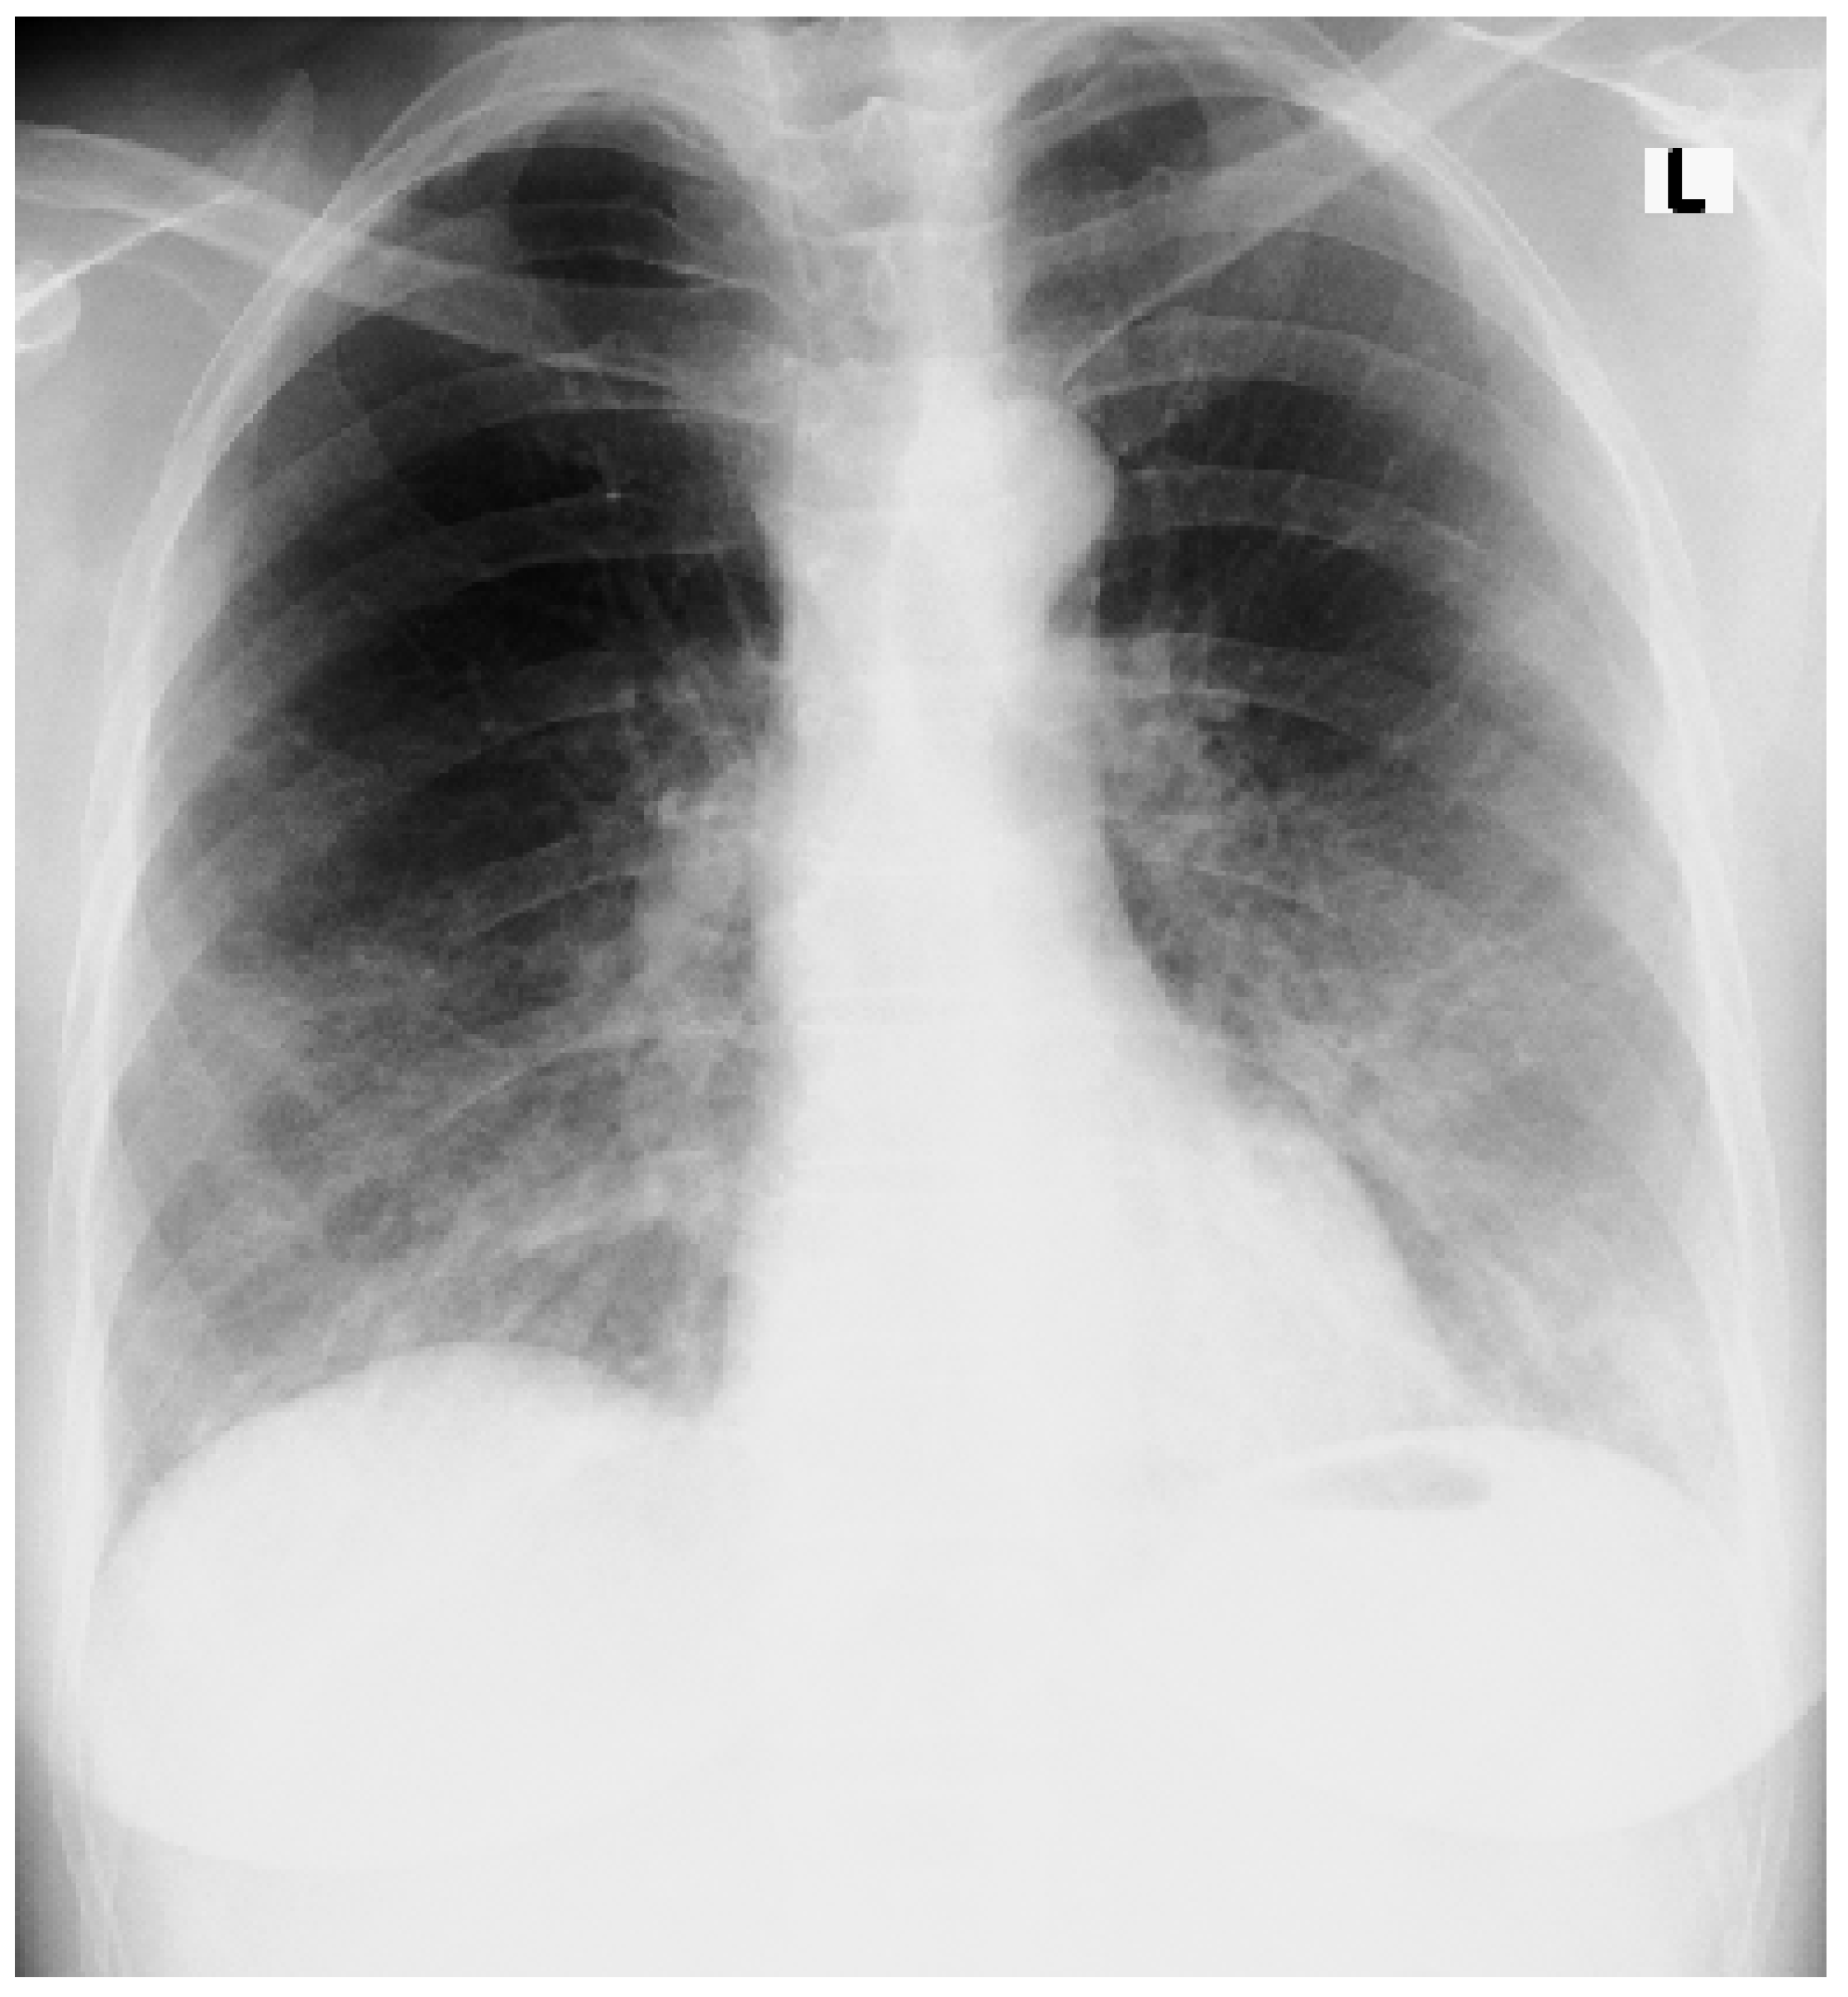

An Accidental Overdose of Colchicine Results in Immediate Recovery of the Patient

Discussion